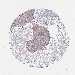

LUNG SQUAMOUS CELL CARCINOMA (TCGA) - Interactive survival scatter ploti

The Survival Scatter plot shows the clinical status (i.e. dead or alive) for all individuals in the patient cohort, based on the same data that underlies the corresponding Kaplan-Meier plots. Patients that are alive at last time for follow-up are shown in blue and patients who have died during the study are shown in red.

The x-axis shows the expression levels (FPKM) of the investigated gene in the tumor tissue at the time of diagnosis. The y-axis shows the follow-up time after diagnosis (years). Both axes are complimented with kernel density curves demonstrating the data density over the axes. The top density plot shows the expression levels (FPKM) distribution among dead (red) and alive patients (blue). The right density plot shows the data density of the survived years of dead patients with high and low expression levels respectively, stratified using the cutoff indicated by the vertical dashed line through the Survival Scatter plot. This cutoff is automatically defined based on the FPKM cutoff that minimizes the p-score. The cutoff can be changed by dragging the vertical line or by entering a cutoff value in the square labeled "Current cut-off".

Under the Survival Scatter plot the p-score landscape (black curve; left axis) is shown together with dead median separation (red curve; right axis). Dead median separation is the difference in median mRNA expression between patients who have died with high and low expression, respectively. It is calculated as follows: median FPKM expression of dead patients with high expression - median FPKM expression of dead patients with low expression. This is intended to aid the user in visually exploring custom cutoffs and the associated p-scores and dead median separation.

Individual patient data is displayed and can be filtered by clicking on one or more of the category buttons on the top of the page. Categories describing expression level and patient information include: high, low, alive, dead, female, male and tumor stages. The scale of the x-axis can be toggled between linear and log-scale by clicking on the "x log" button. Mouse-over function shows TCGA ID, patient information and mRNA expression (FPKM) for each patient.

& Survival analysisi

Kaplan-Meier plots summarize results from analysis of correlation between mRNA expression level and patient survival. Patients were divided based on level of expression into one of the two groups "low" (under cut off) or "high" (over cut off). X-axis shows time for survival (years) and y-axis shows the probability of survival, where 1.0 corresponds to 100 percent.

CD80 is not prognostic in Lung Squamous Cell Carcinoma (TCGA)

Best expression cut offi

Based on the FPKM value of each gene, patients were classified into two groups and association between prognosis (survival) and gene expression (FPKM) was examined. The best expression cut-off refers the FPKM value that yields maximal difference with regard to survival between the two groups at the lowest log-rank P-value. Best expression cut-off was selected based on survival analysis .

When clicking on this number, the vertical dashed line indicating cut-off, the interactive survival plot, and the Kaplan-Meier curve will be adjusted to show results based on the best expression cut-off.

: 0.59

Median expressioni

Median expression refers to the median FPKM value calculated based on the gene expression (FPKM) data from all patients in this dataset. When clicking on this number, the vertical dashed line indicating cut-off, the interactive survival plot, and the Kaplan-Meier curve will be adjusted to show results based on the median expression.

: N/A

Median follow up timei

Median follow up time refers to the median time (years) after diagnosis with this type of cancer, based on clinical data from all patients in this dataset.

P scorei

Log-rank P value for Kaplan-Meier plot showing results from analysis of correlation between mRNA expression level and patient survival.

N/A

5-year survival highi

5-year survival for patients with higher expression than the expression cutoff.

For melanoma and glioma, 3-year survival is shown.

5-year survival lowi

5-year survival for patients with lower expression than the expression cutoff.

TCGA RNA samplesi

RNA-seq data is reported as average FPKM (number Fragments Per Kilobase of exon per Million reads), generated by the The Cancer Genome Atlas (TCGA) .

Normal distribution across the dataset is visualized with box plots, shown as median and 25th and 75th percentiles. Points are displayed as outliers if they are above or below 1.5 times the interquartile range. FPKM values of the individual samples are presented next to the box plot.

Average pTPM 1.2

Number of samples 489